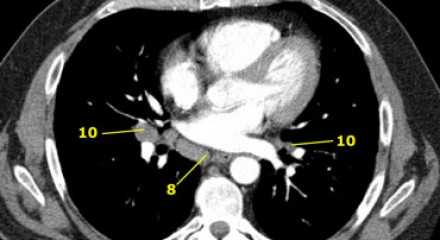

4L. Левые нижние паратрахеальные лимфатические узлы

4L узлы расположенные слева от левой стенки трахеи, между горизонтальными линиями проведенными касательно верхней стенке дуги аорты и линией проходящей через левый главный бронх на уровне верхнего края верхнедолевого бронха. Они включают паратрахеальные узлы расположенные кнутри от артериальной связки.

Узлы 5 группы (аортопульмонального окна) расположены кнаружи от артериальной связки.

На левом изображении над уровнем легочного ствола представлены нижние паратрахеальные узлы слева и справа, так же здесь представлены узлы 3 и 5 групп.

Изображение слева выше уровня карины. Слева от трахеи 4L узлы. Обратите внимание что они расположены между легочным стволом и аортой, но не в аортопульмональном окне, потому что они лежат медиальнее артериальной связки. Лимфатические узлы латеральнее легочного ствола относятся к 5 группе.

![11]() 7. Подкаринальные лимфатические узлыЭти лимфатические узлы расположены ниже уровня бифуркации трахеи (карины), но не относятся к нижнедолевым бронху и артерии. Справа они располагаются каудальнее нижней стенки промежуточного бронха. Слева они располагаются каудальнее верхней стенки нижнедолевого бронха. Слева лимфатический узел 7 группы справа от пищевода. ![12]() 8. Параэзофагеальные лимфатические узлыЭти лимфатические узлы ниже подкаринальных лимфатических узлов и распространяются каудальнее до диафрагмы. На изображении слева ниже уровня карины справа от пищевода обозначен лимфатический узел 8 группы. На ПЭТ изображении слева показано накопление 18Р-дезоксиглюкозы в узле 8 группы. На соответствующем КТ изображении видно что данный лимфатический узел (голубая стрелка) не увеличен. Вероятность того что в имеется метастатическое поражение данного узла чрезвычайно высока, поскольку специфичность ПЭТ выше чем измерение размеров лимфатических узлов. ![14]() 9. лимфатические узлы легочной связкиДанные лимфатические узлы лежат в пределах легочной связки, в том числе и по ходу нижней легочной вены. Легочная связка представлена дупликатурой медиастинальной плевры охватывающей корень легкого. ![15]() 10. лимфатические узлы корня легкогоЛимфатические узлы корня расположены проксимальнее долевых узлов, но дистальнее медиастинальной дупликатуры и узлов промежуточного бронха справа. Все лимфатические узлы 10-14 групп являются N1 узлами, так как они находятся вне средостения. 1. лимфатические узлы вырезки грудины видны только на этом уровне и выше него 2. верхние паратрахеальные лимфатические узлы: ниже ключиц , справа над пересечением нижнего края левого плечеголовного ствола и трахеи, а слева над дугой аорты